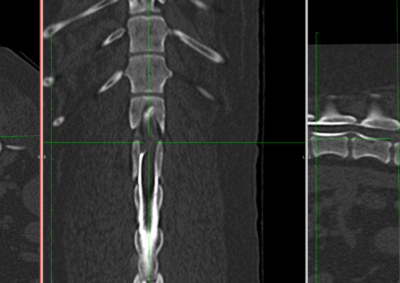

脳神経外科 注意 ボタンをクリックした先に、治療中および手術中の画像が説明で使用されている場合がございます。 そのような画像に弱い方は閲覧なさらないようお願いいたします。 脳神経外科 セメントレス環軸固定術 脳神経外科 Hemi-Laminectomy 脳神経外科 Ventral Slot 脳神経外科 椎体固定術 脳神経外科 Hemi-Laminectomy 脳神経外科 脊髄亜膜下憩室切除 脳神経外科 椎間板ヘルニア G1 脳神経外科 椎間板ヘルニア G2 脳神経外科 IVDD G5 脳神経外科 Ventral Slot 脳神経外科 Ventral Slot 脳神経外科 Ventral Slot 123456> 症例カテゴリー 放射線治療整形外科軟部組織外科脳神経外科内科腫瘍外科救急・集中治療リハビリテーション科腫瘍内科内視鏡科脳神経科呼吸器外科中医・漢方猫の腎移植循環器科電気化学療法